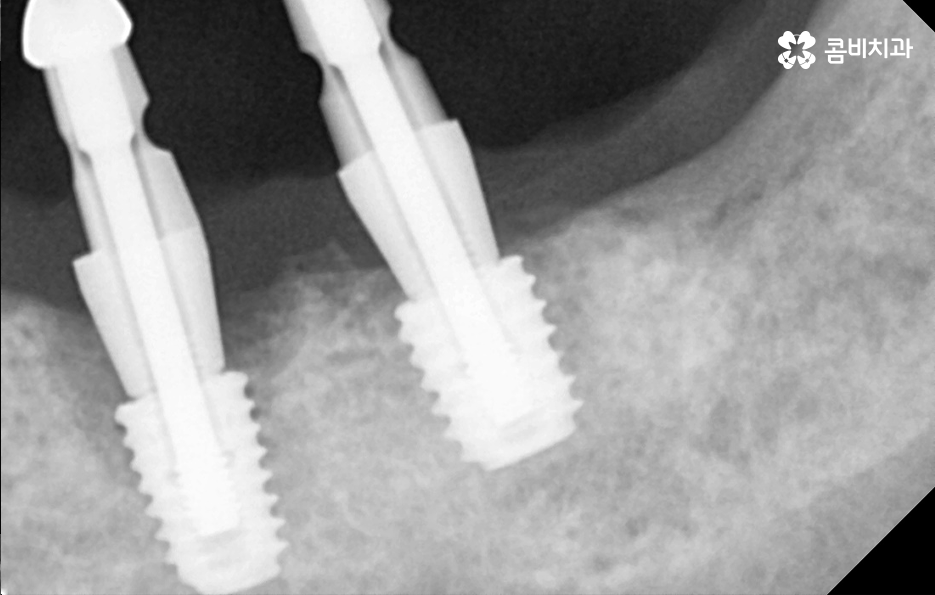

임플란트의 치료 원리를 살펴보면 임플란트는 잇몸 뼈에 심고 골 유착 과정을 통해서 저작력을 얻기 때문에 치료 전과 치료 후 모두 잇몸 상태가 매우 중요한 치료라는 것을 알 수 있어요

잇몸 뼈가 부족한 경우 뼈이식을 통해 임플란트를 식립하기 좋은 잇몸 상태를 만드는 것이 치료 결과에도 중요하며 임플란트의 식립 위치부터 각도, 깊이 등은 치과의 첨단 장비뿐 아니라 치과의사의 경험과 실력이 중요한 부분이기 때문에 임플란트의 전체 과정을 고려하여 비용도 중요하지만 건강한 치료 결과를 위해 종합적으로 따져보고 치과를 선택하시길 권하고 있어요